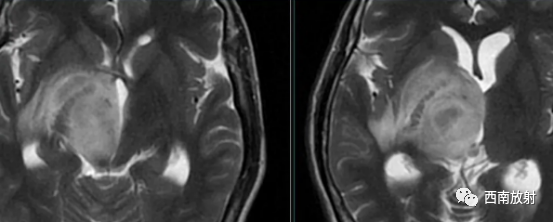

中枢神经系统淋巴瘤主要发生在脑内深部白质,病灶大多位于幕上。多数病灶邻近脑室。病灶形态多为团块状,较典型表现如同“握拳”者。位于胼胝体压部的病灶沿纤维构形,形似蝴蝶,颇具特征。该病“瘤周水肿”在T2WI呈高信号,不仅反映该部位脑组织水分增加,还有肿瘤细胞沿血管周围间隙浸润、播散的因素;另一特征为“瘤周水肿”与肿瘤体积不一致。本病大多数肿瘤体积相对较大,具有较明显占位效应,但周边水肿相对轻微。非免疫功能低下者发生淋巴瘤时,瘤体内囊变、坏死少见。本病也可发生在中枢神经系统的其他部位,脑外受累部位有颅骨、颅底、脊髓等。

▲病例:脑淋巴瘤。脑深部结节病灶,具有刀切征、凹陷征或肚脐凹征、尖角、多发。DWI呈稍高信号,形态上怪异,波普NAA及Cho减低,出现导致LL峰。颈部、胸廓入口区及腋窝多发淋巴结肿大并相互融合。